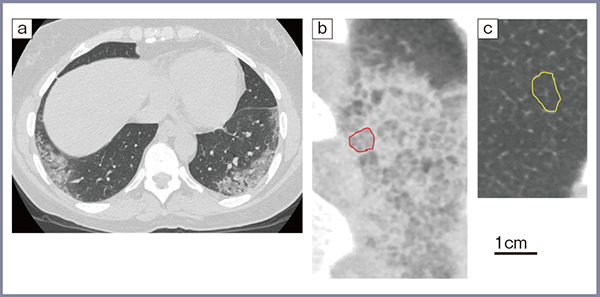

NSIPは,特発性間質性肺炎の病理・画像パターンの一つで,強皮症などの膠原病肺で多く見られる。NSIPは,病理学的には小葉内にびまん性に広がる肺胞壁の細胞浸潤や線維化を特徴とし,従来のCTでは,「すりガラス影」と表現されることも多かったが,高精細CTでは細かい線から構成される網状病変として認識できるようになった。図5に,生データの段階でノイズを加えることで従来のCTで撮影したかのように加工したシミュレーション画像(a)と高精細CTの画像(b)の比較を示す。高精細CTでは1本1本の線がよりシャープに観察できる。われわれは,これについてRSNA 2021で発表した。

図5 30歳代,男性,NSIPのシミュレーション画像と高精細CTの比較